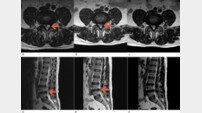

• 자생한방병원, 한의치료 척추낭종 통증 호전 및 흡수 확인

자생한방병원, 한의치료 척추낭종 통증 호전 및 흡수 확인자생한방병원 척추관절연구소(소장 하인혁) 최희승 한의사 연구팀은 비수술 한의통합치료를 받은 척추낭종(요추후관절낭종) 환자의 통증 호전 및 낭종 자연 흡수를 확인한 4례의 임상 증례를 발표했다. 낭종(물혹)은 인체의 어디에서나 나타날 수 있다. 척추에 생긴 낭종의 경우 특별한 증상이 …2023-07-24 11:31